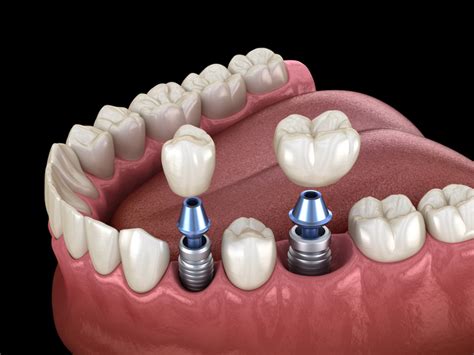

Un implante dental es un dispositivo de titanio que se inserta en los huesos maxilares y que sirve de anclaje para la colocación de prótesis dentales.

Tipos de Prótesis Dentales

Las prótesis dentales pueden ser unitarias (un solo diente), por tramos (ausencia de varios dientes de una arcada) o arcadas completas. La colocación del número de implantes depende de numerosos factores, principalmente biomecánicos y de características del hueso del paciente.

Los implantes dentales permiten reponer las ausencias dentarias de una forma definitiva y altamente predecible. El objetivo es que la función normal de su boca sea restablecida, manteniendo una estética de altísima calidad, que den a su prótesis una apariencia completamente natural.

Los implantes que se utilizan están fabricados en titanio, un material biocompatible, que en la mayoría de los casos no produce reacción de rechazo. Son estructuras metálicas que, por medio de una intervención quirúrgica, se introducen en el hueso maxilar o en la mandíbula.